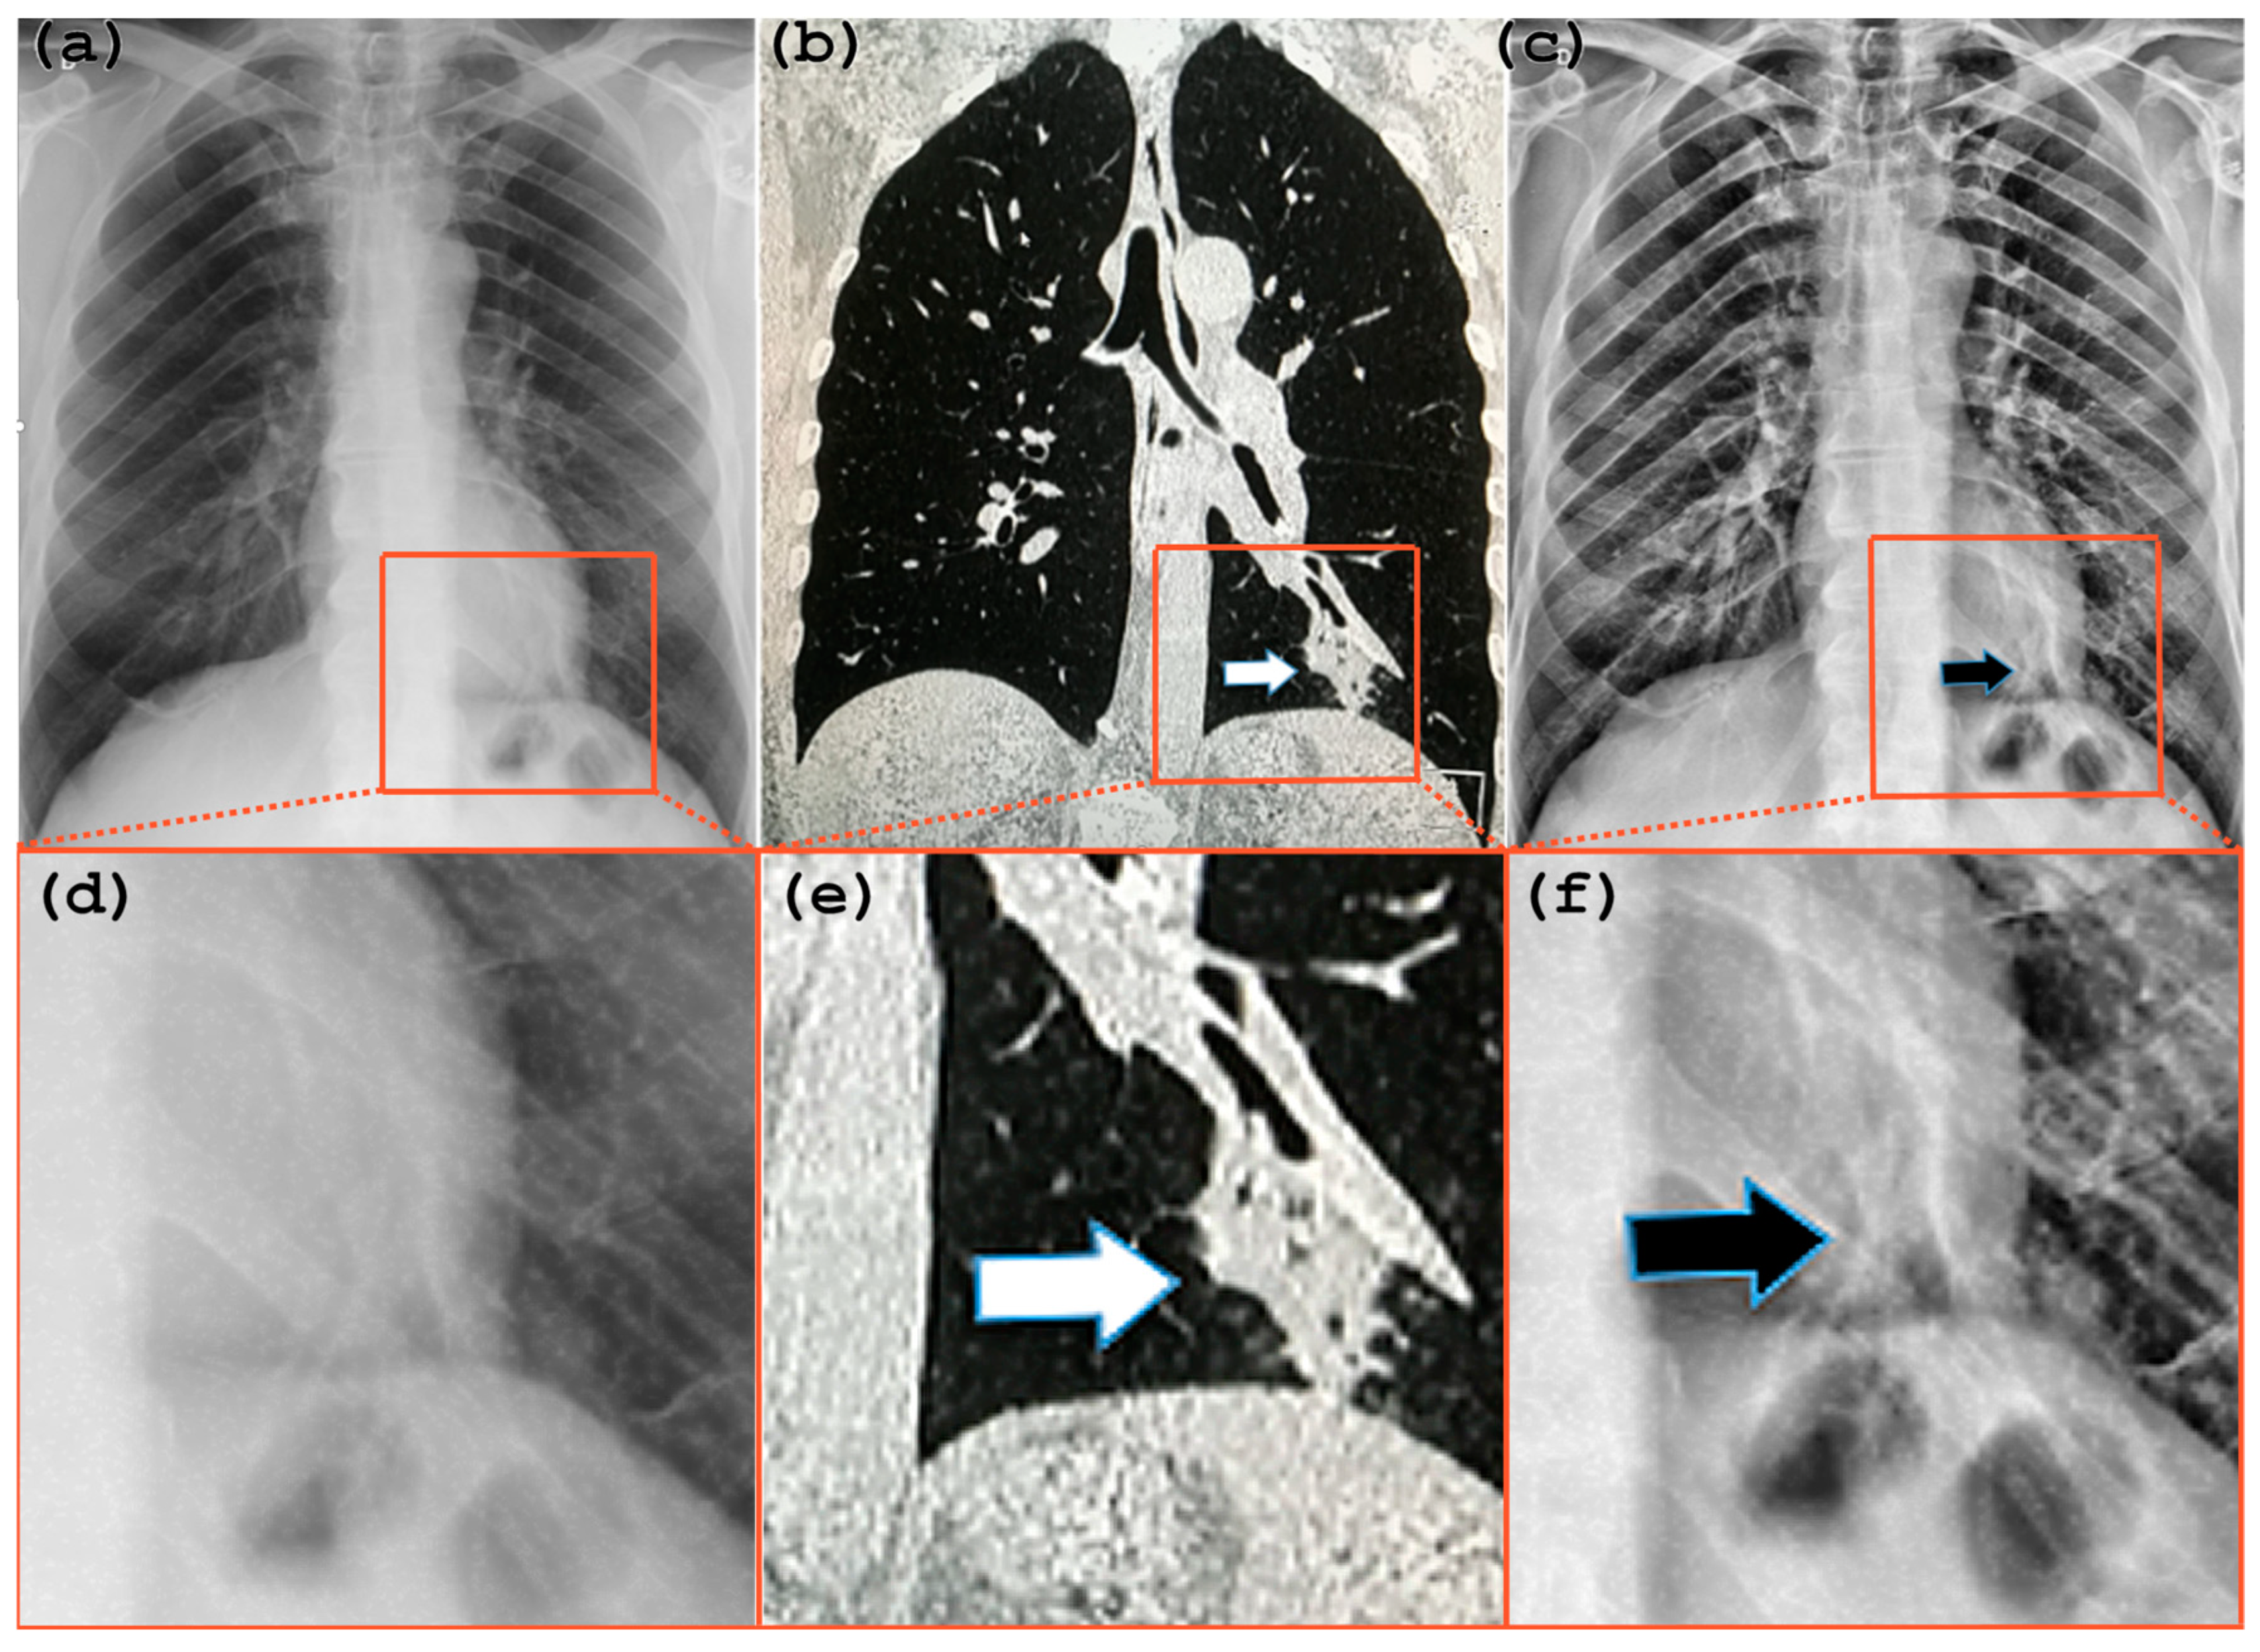

4.2. Radiological Evaluation and Statistics